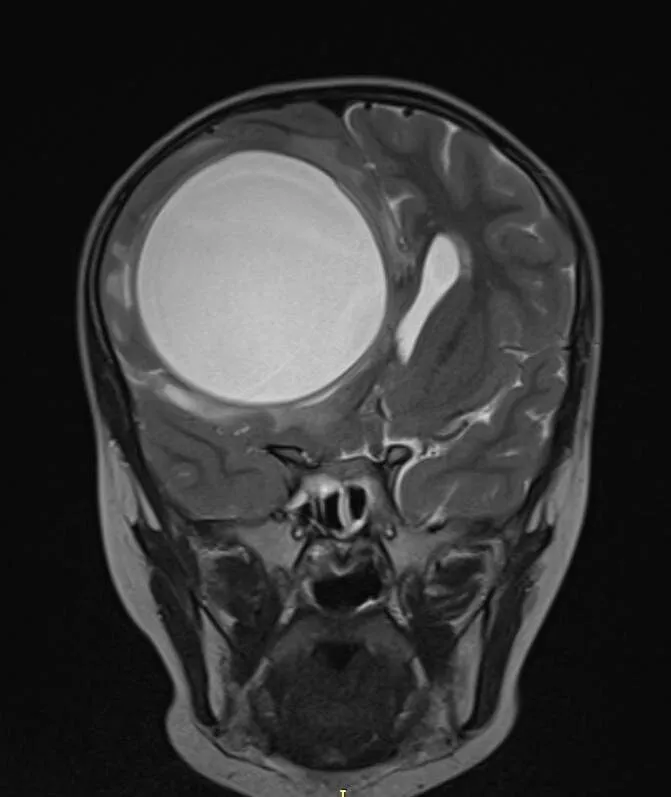

Новосибирск. 6 февраля. ИНТЕРФАКС - Хирурги Новосибирской областной клинической больницы удалили из головного мозга пятилетней девочки огромную кисту с паразитом внутри, сообщает пресс-служба Минздрава региона.

"Когда девочку госпитализировали, у нее не двигались левые рука и нога. Во время обследования врачи обнаружили два небольших образования в лёгких и огромное - больше 10 см диаметром - в головном мозге. Диагноз "эхинококкоз" подтвердился", - говорится в сообщении.

"Главная трудность такого вмешательства - капсулу нужно извлечь целиком, не нарушив целостность оболочки, толщина которой всего 1-2 миллиметра", - говорится в сообщении.

Содержимое паразитарной кисты очень токсично, в случае с головным мозгом нельзя откачать его через прокол, а после провести обработку специальными препаратами, как это делается, например, при операциях на печени.

Операция длилась несколько часов. Нейрохирурги сумели аккуратно высвободить и извлечь кисту.